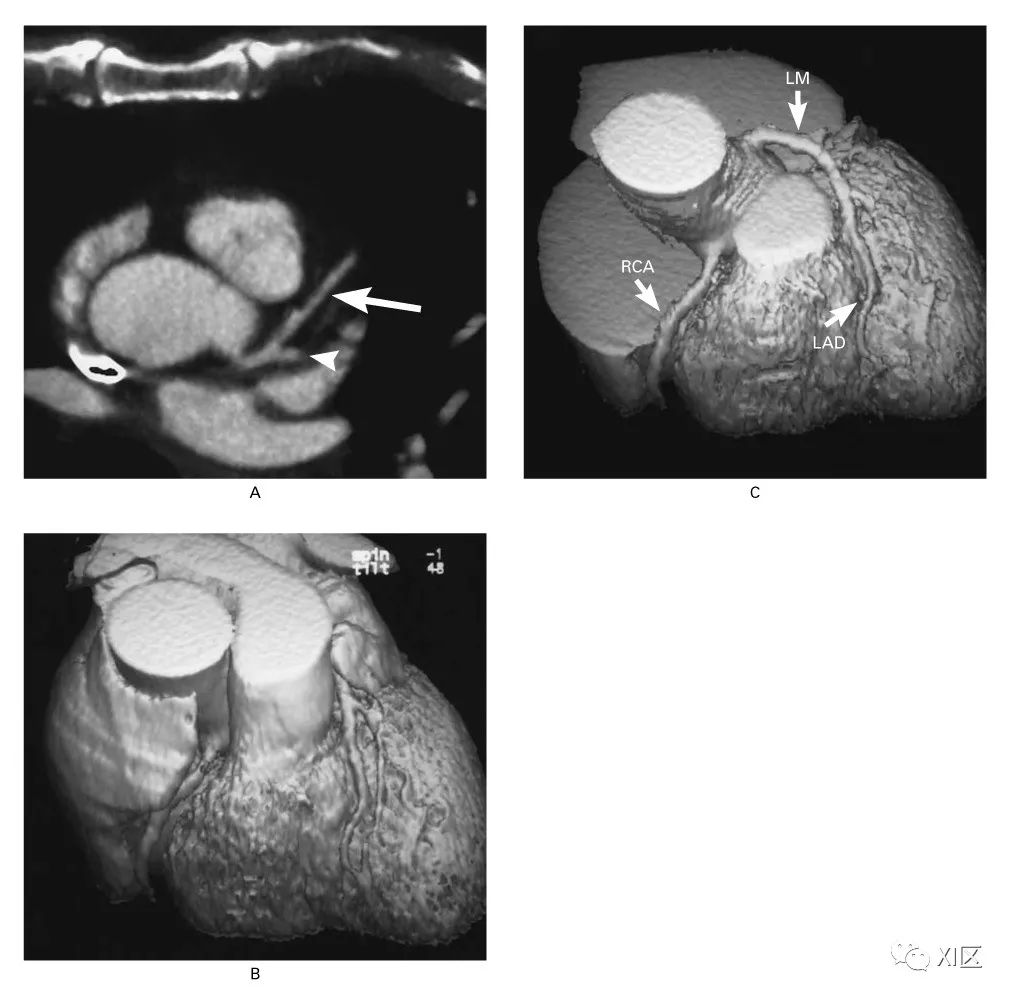

Coronary CTA images of electron beam CT

Achenbach S . Value of electron-beam computed tomography for the noninvasive detection of high-grade coronary-artery stenoses and occlusions.[J]. New England Journal of Medicine, 1998, 339(27):1964.